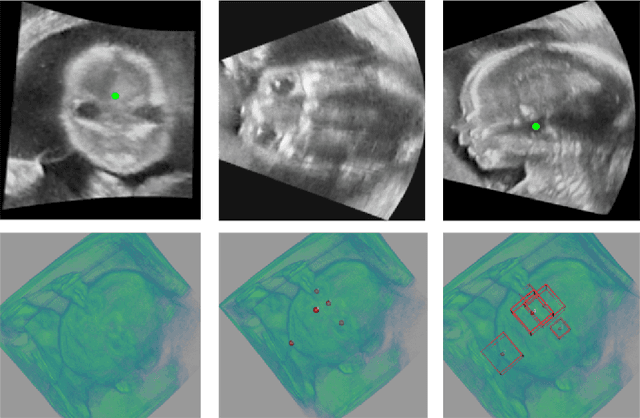

Abstract:3D ultrasound (US) can facilitate detailed prenatal examinations for fetal growth monitoring. To analyze a 3D US volume, it is fundamental to identify anatomical landmarks of the evaluated organs accurately. Typical deep learning methods usually regress the coordinates directly or involve heatmap-matching. However, these methods struggle to deal with volumes with large sizes and the highly-varying positions and orientations of fetuses. In this work, we exploit an object detection framework to detect landmarks in 3D fetal facial US volumes. By regressing multiple parameters of the landmark-centered bounding box (B-box) with a strict criteria, the proposed model is able to pinpoint the exact location of the targeted landmarks. Specifically, the model uses a 3D region proposal network (RPN) to generate 3D candidate regions, followed by several 3D classification branches to select the best candidate. It also adopts an IoU-balance loss to improve communications between branches that benefits the learning process. Furthermore, it leverages a distance-based graph prior to regularize the training and helps to reduce false positive predictions. The performance of the proposed framework is evaluated on a 3D US dataset to detect five key fetal facial landmarks. Results showed the proposed method outperforms some of the state-of-the-art methods in efficacy and efficiency.